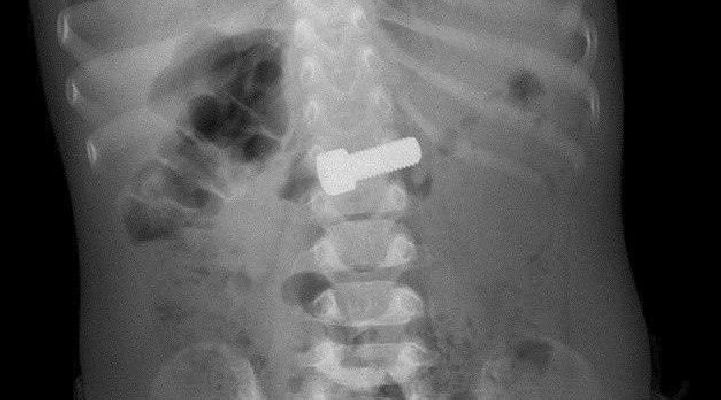

Врачи вытащили из желудка годовалого ребёнка большой металлический болт